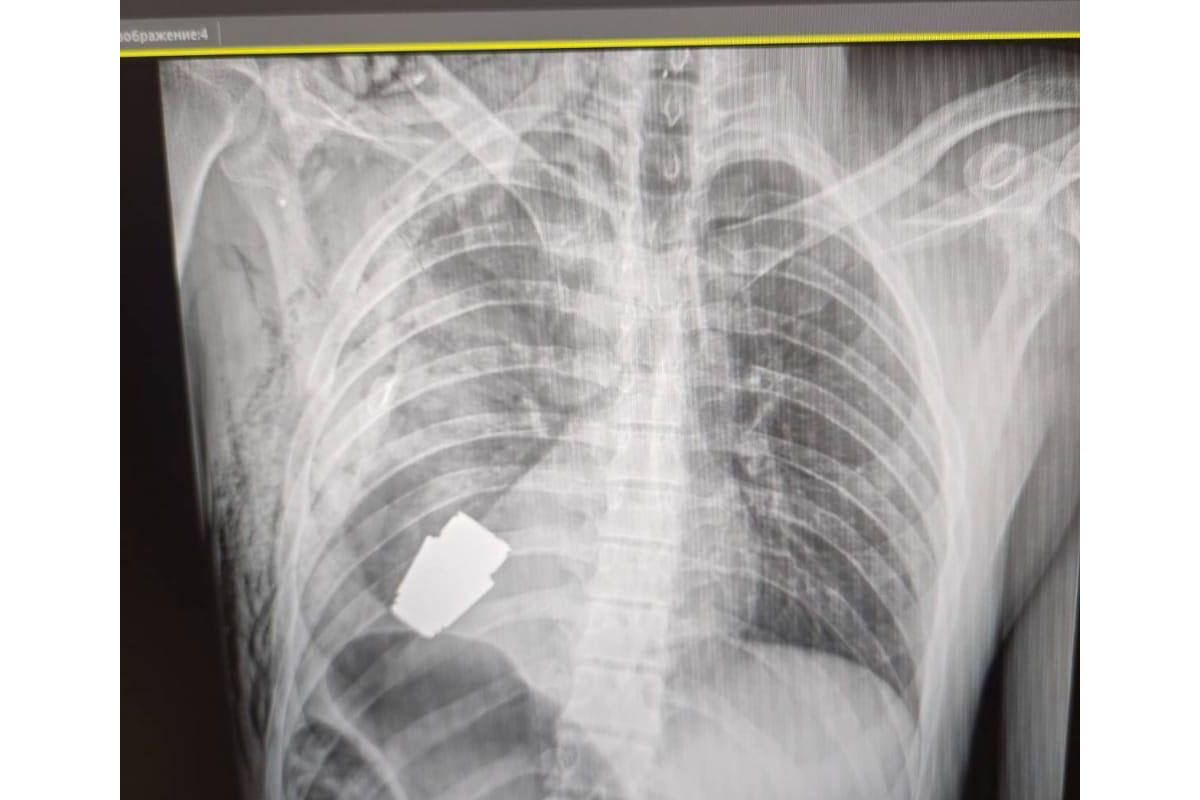

Операція під наглядом саперів: з тіла бійця ЗСУ дістали гранату ВОГ, що не розірвалася

☝️ Операція проводилася одним з найдосвідченіших хірургів ЗСУ – Андрієм Вербою без електрокоагуляції, оскільки граната могла детонувати у будь-який момент.